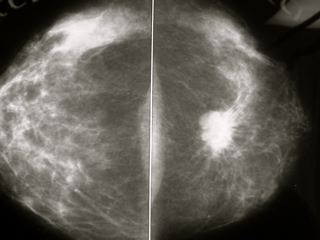

Eficacia del cribado del cáncer de mama: Revisión actualizada de la U.S. Preventive Services Task Force-